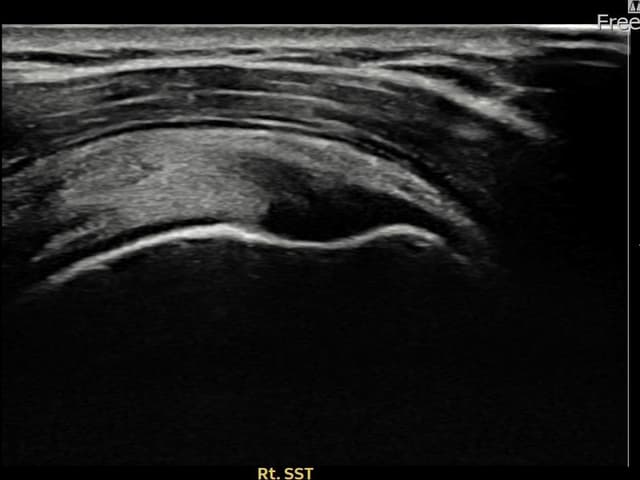

[촬영시기:22.08.10]

[석회분쇄흡입술] 우측 어깨 극심한 야간 통증으로 수면이 불가능해진 50대 여성 환자로, X-ray에서 우측 극상근건 내 석회 침착이 확인되어 석회분쇄흡입술을 시행하였습니다.